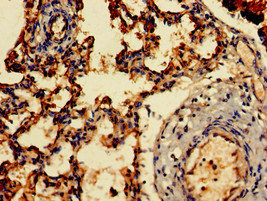

Immunohistochemistry of paraffin-embedded human lung tissue using CSB-PA00929A0Rb at dilution of 1:100